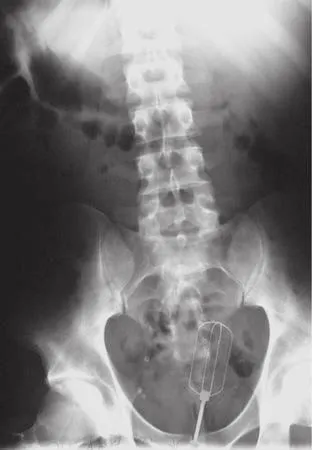

Une ampoule

1/9

Dans leur livre Stuck Up!: 100 Objects Inserted and Ingested in Places They Shouldn"t Be, trois médecins américains ont publié les photos d"objets incroyables retrouvés en examinant leur patient. Ici, une ampoule.